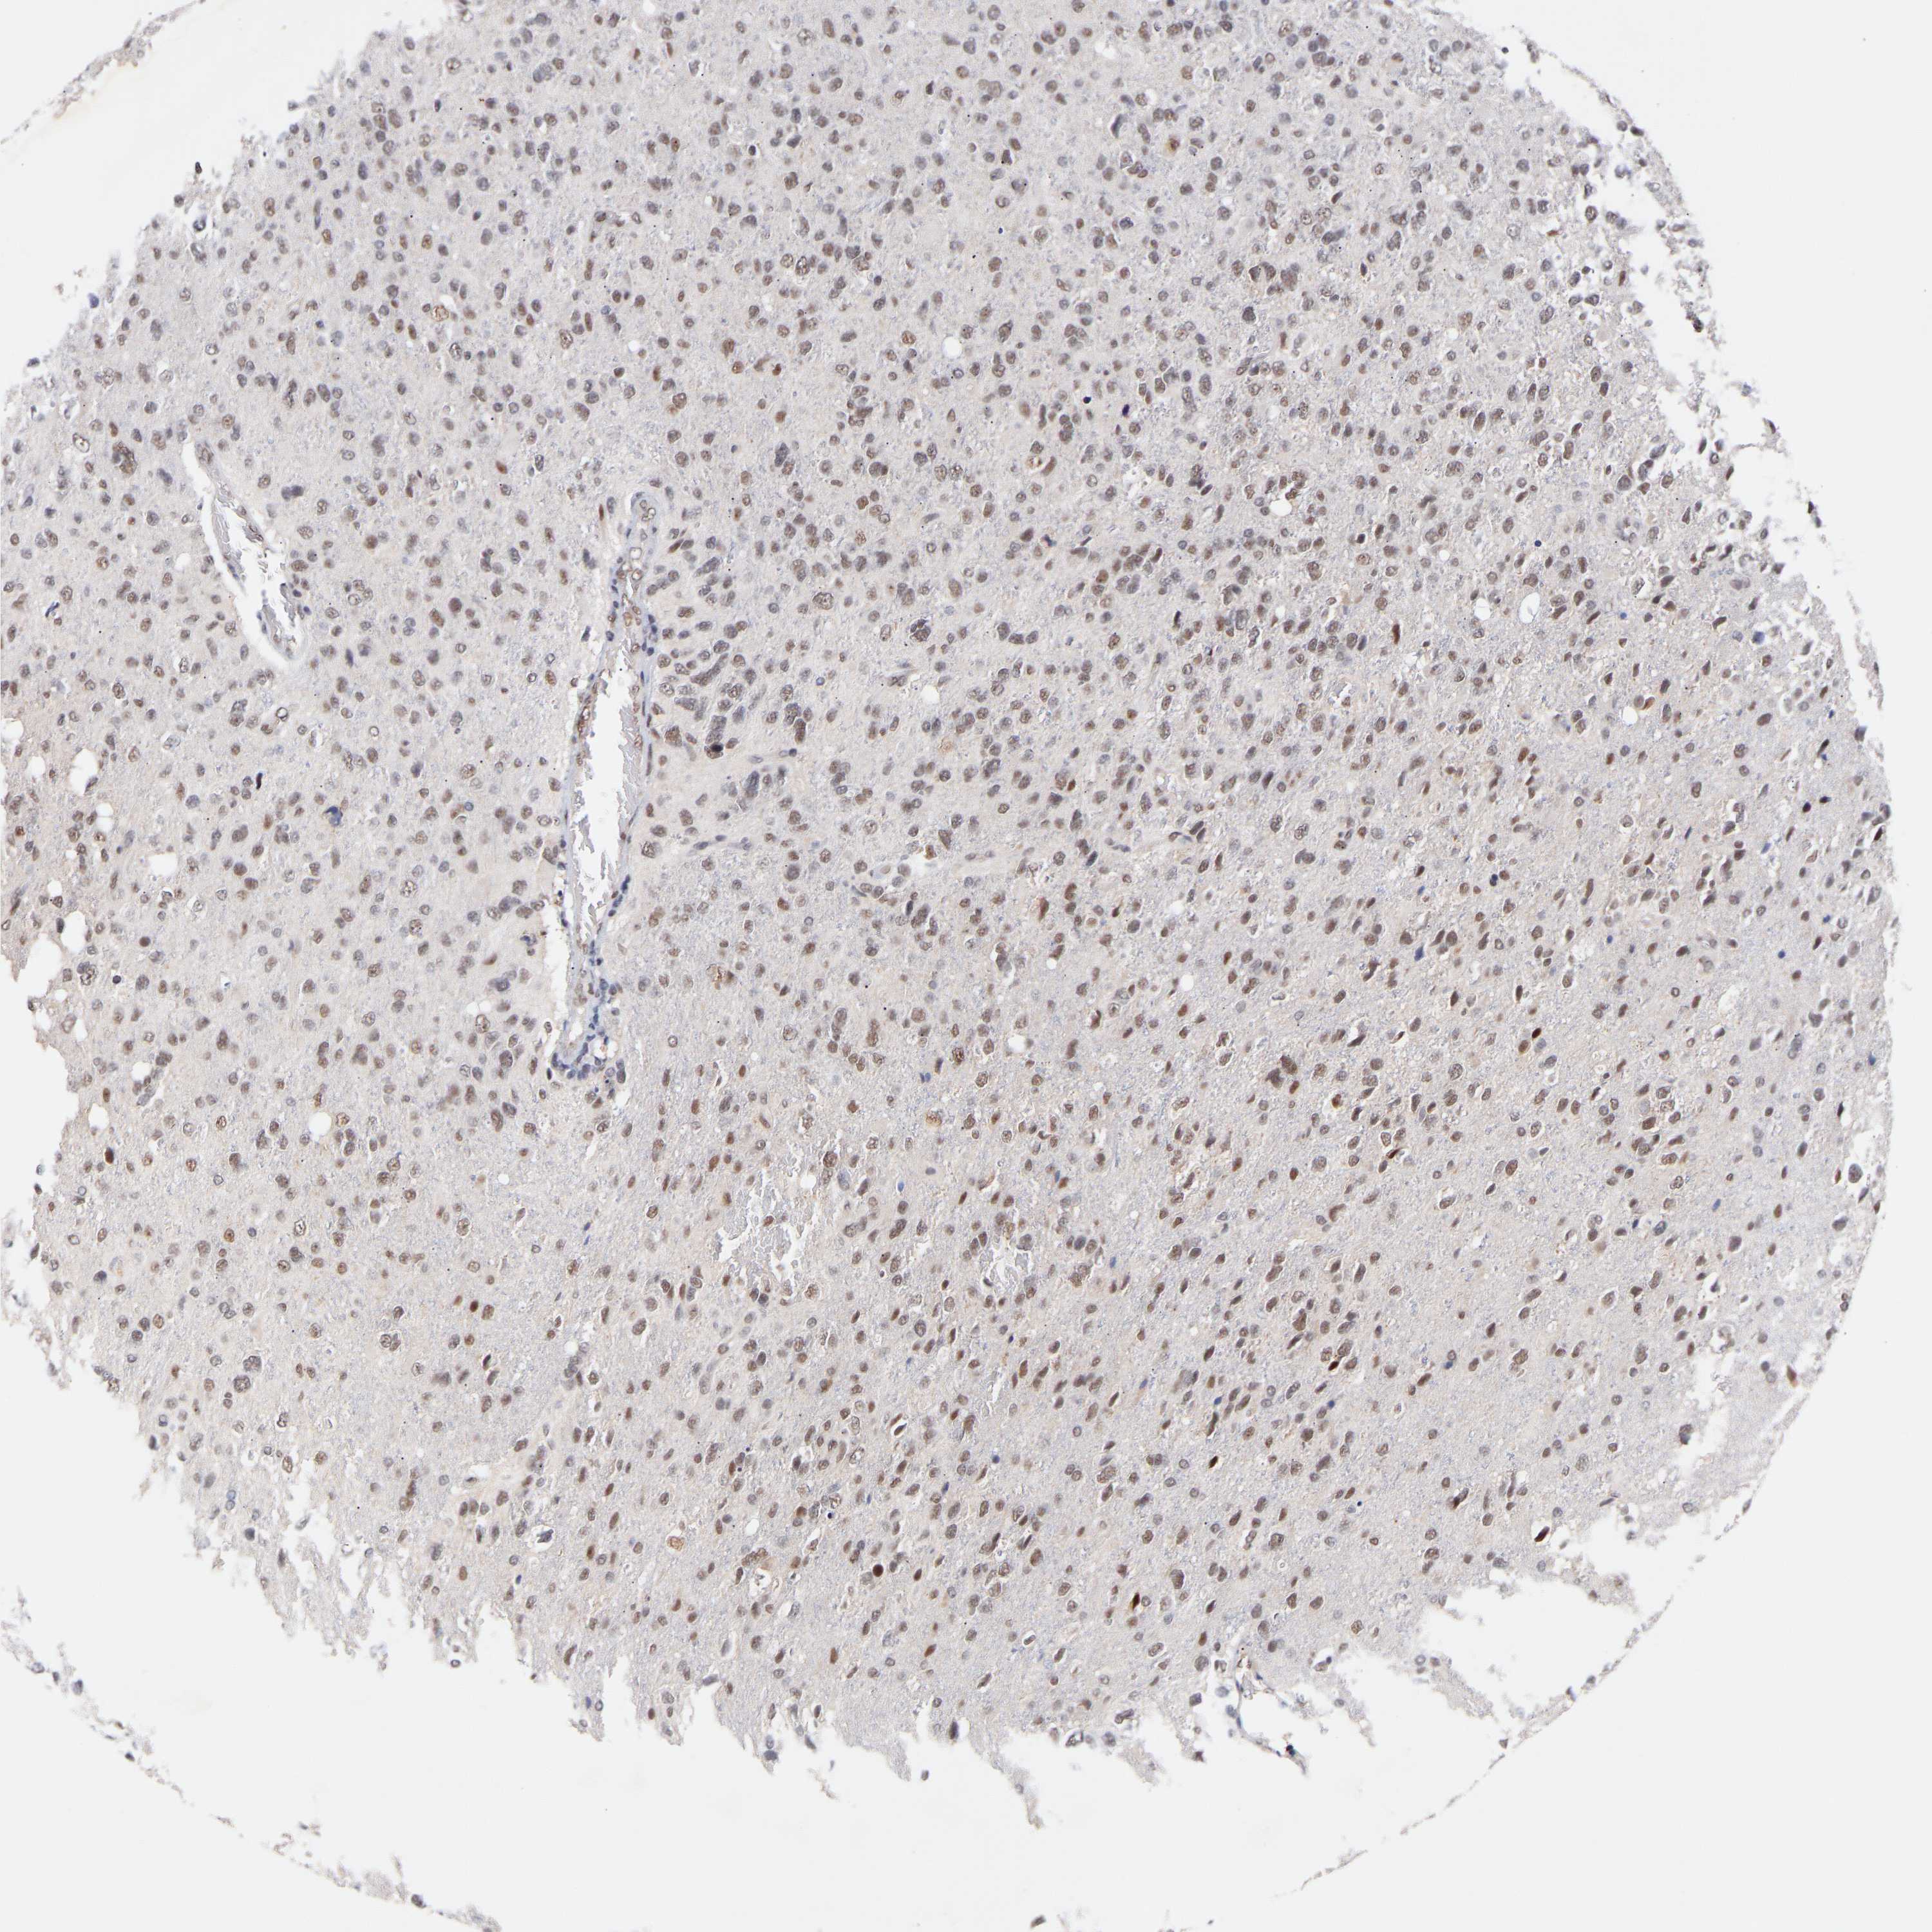

GLIOMA - Protein expressioni

A mouse-over function shows sample information and annotation data. Click on an image to view it in a full screen mode. Samples can be filtered based on level of antibody staining by selecting one or several of the following categories: high, medium, low and not detected. The assay and annotation is described here.

Note that samples used for immunohistochemistry by the Human Protein Atlas do not correspond to samples in the TCGA dataset.

Antibody stainingi

Antibody staining in the annotated cell types in the current human tissue is reported as not detected, low, medium, or high, based on conventional immunohistochemistry profiling in selected tissues. This score is based on the combination of the staining intensity and fraction of stained cells.

Each image is clickable and will lead to virtual microscopy that enables deeper exploration of all samples and also displays staining intensity scores, fraction scores and subcellular localization as well as patient and tissue information for each sample.

Antibody HPA019824

Antibody CAB015201

Staining

High

Medium

Low

Not detected

Intensity

Strong

Moderate

Weak

Negative

Quantity

>75%

75%-25%

<25%

None

Location

Nuclear

Cytoplasmic/membranous

Cytoplasmic/membranous,nuclear

Glioma, malignant, High grade

Glioma, malignant, Low grade